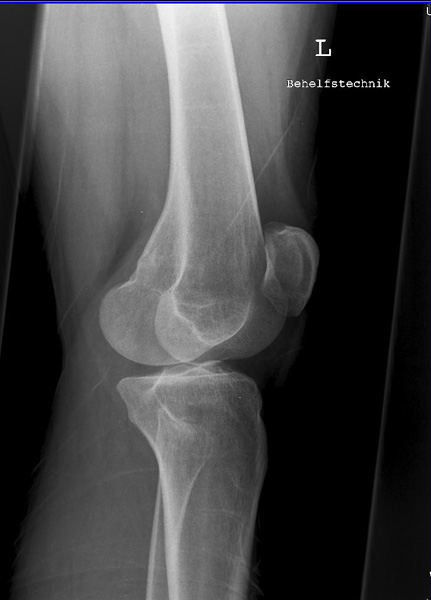

Knie a.p.

121_3.jpg

Fehler

Die Patella ragt über die laterale Begrenzung des distalen Femur hinaus, gleichzeitig projiziert sich das ganze Fibularköpfchen in dem Tibiakopf. Überdies wird dann das Tuberculum intercondylare mediale von der medialen Gelenkrolle des Femus verschattet. Bei dieser Fehleinstellung lassen sich z.B. posttraumatische Verkalkungen, die medial am inneren Gelenkknorren des Oberschenkels liegen (sog. Stieda-Pellegrinische Schatten), nicht mehr erkannt werden.

Abhilfe

Der nach außen schauende Fuß muss leicht, also nicht zu stark, nach innen gedreht werden, Großzehenwärts.